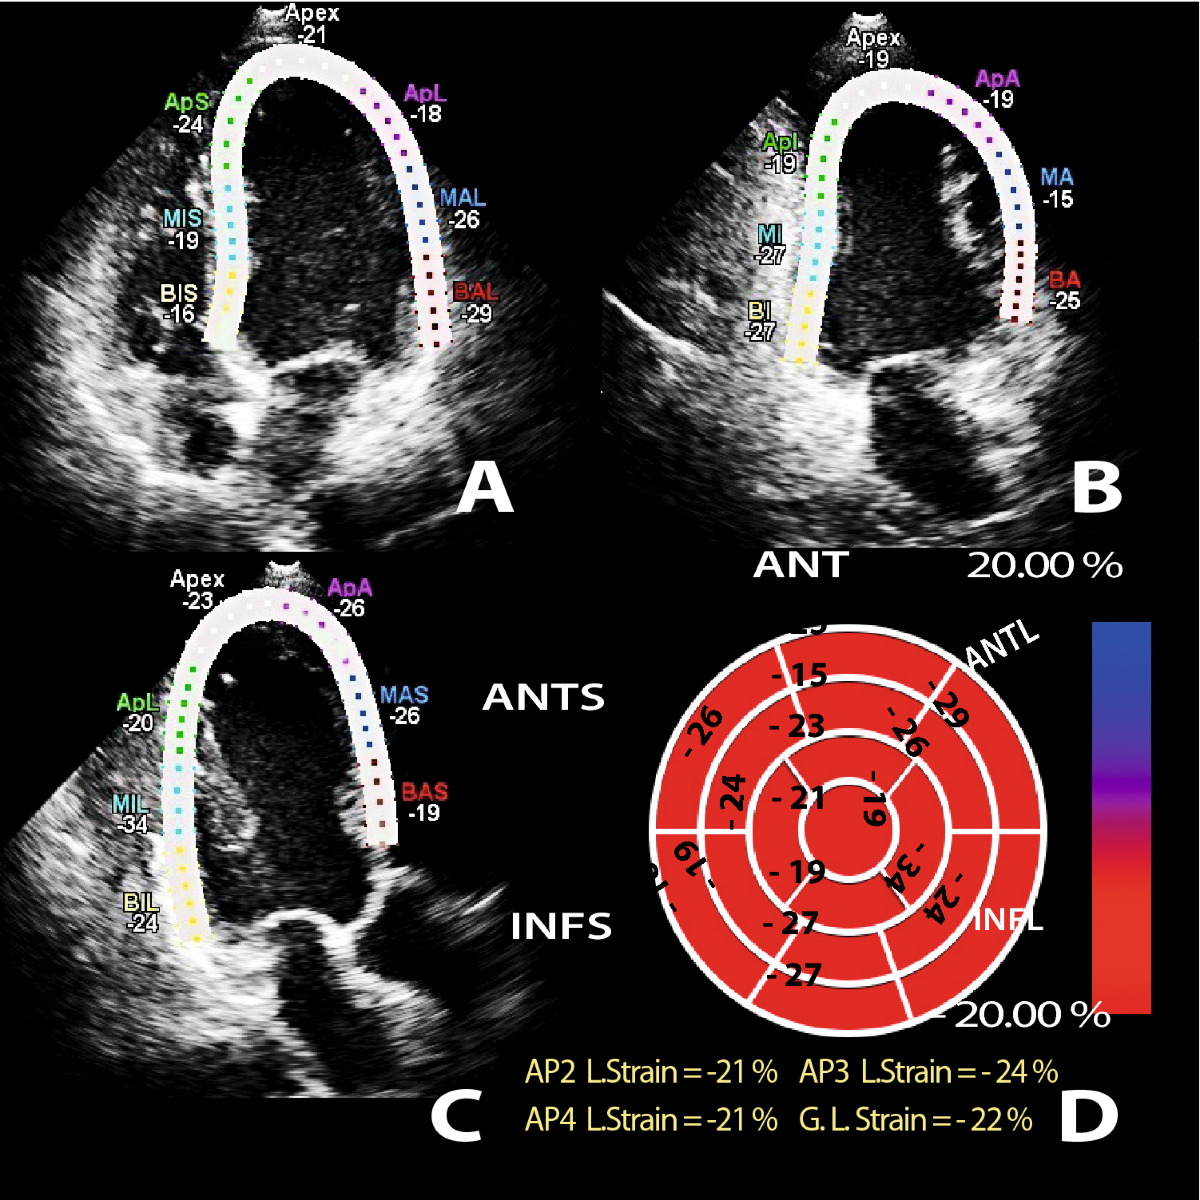

» Interpreting strain echo (98) 사진

Interpreting strain echo (98) 사진